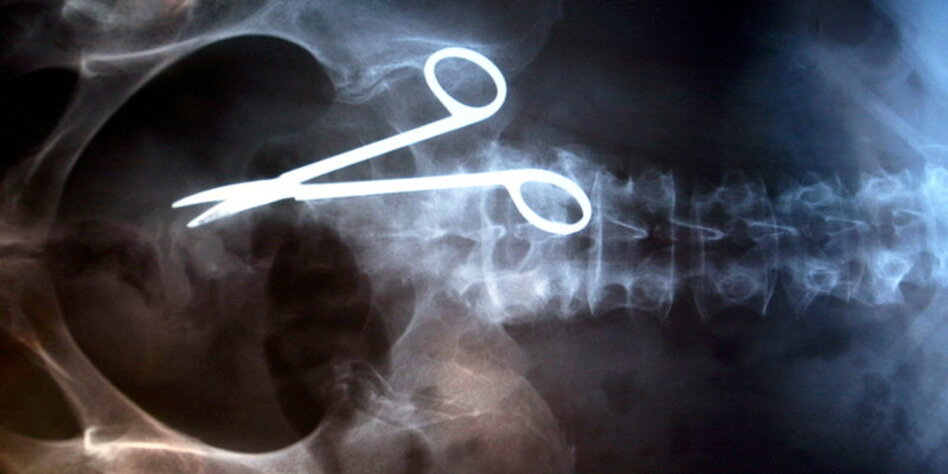

(IMG) Bild: Das Gesetz bietet mehr Schutz vor groben Ärztefehlern.

zurück. So sieht der Gesetzentwurf zwar vor, dass künftig bei groben

Behandlungsfehlern - also etwa der Amputation des rechten statt des linken

Fußes - die Beweislast beim Arzt liegt. Das aber entspricht schon heute